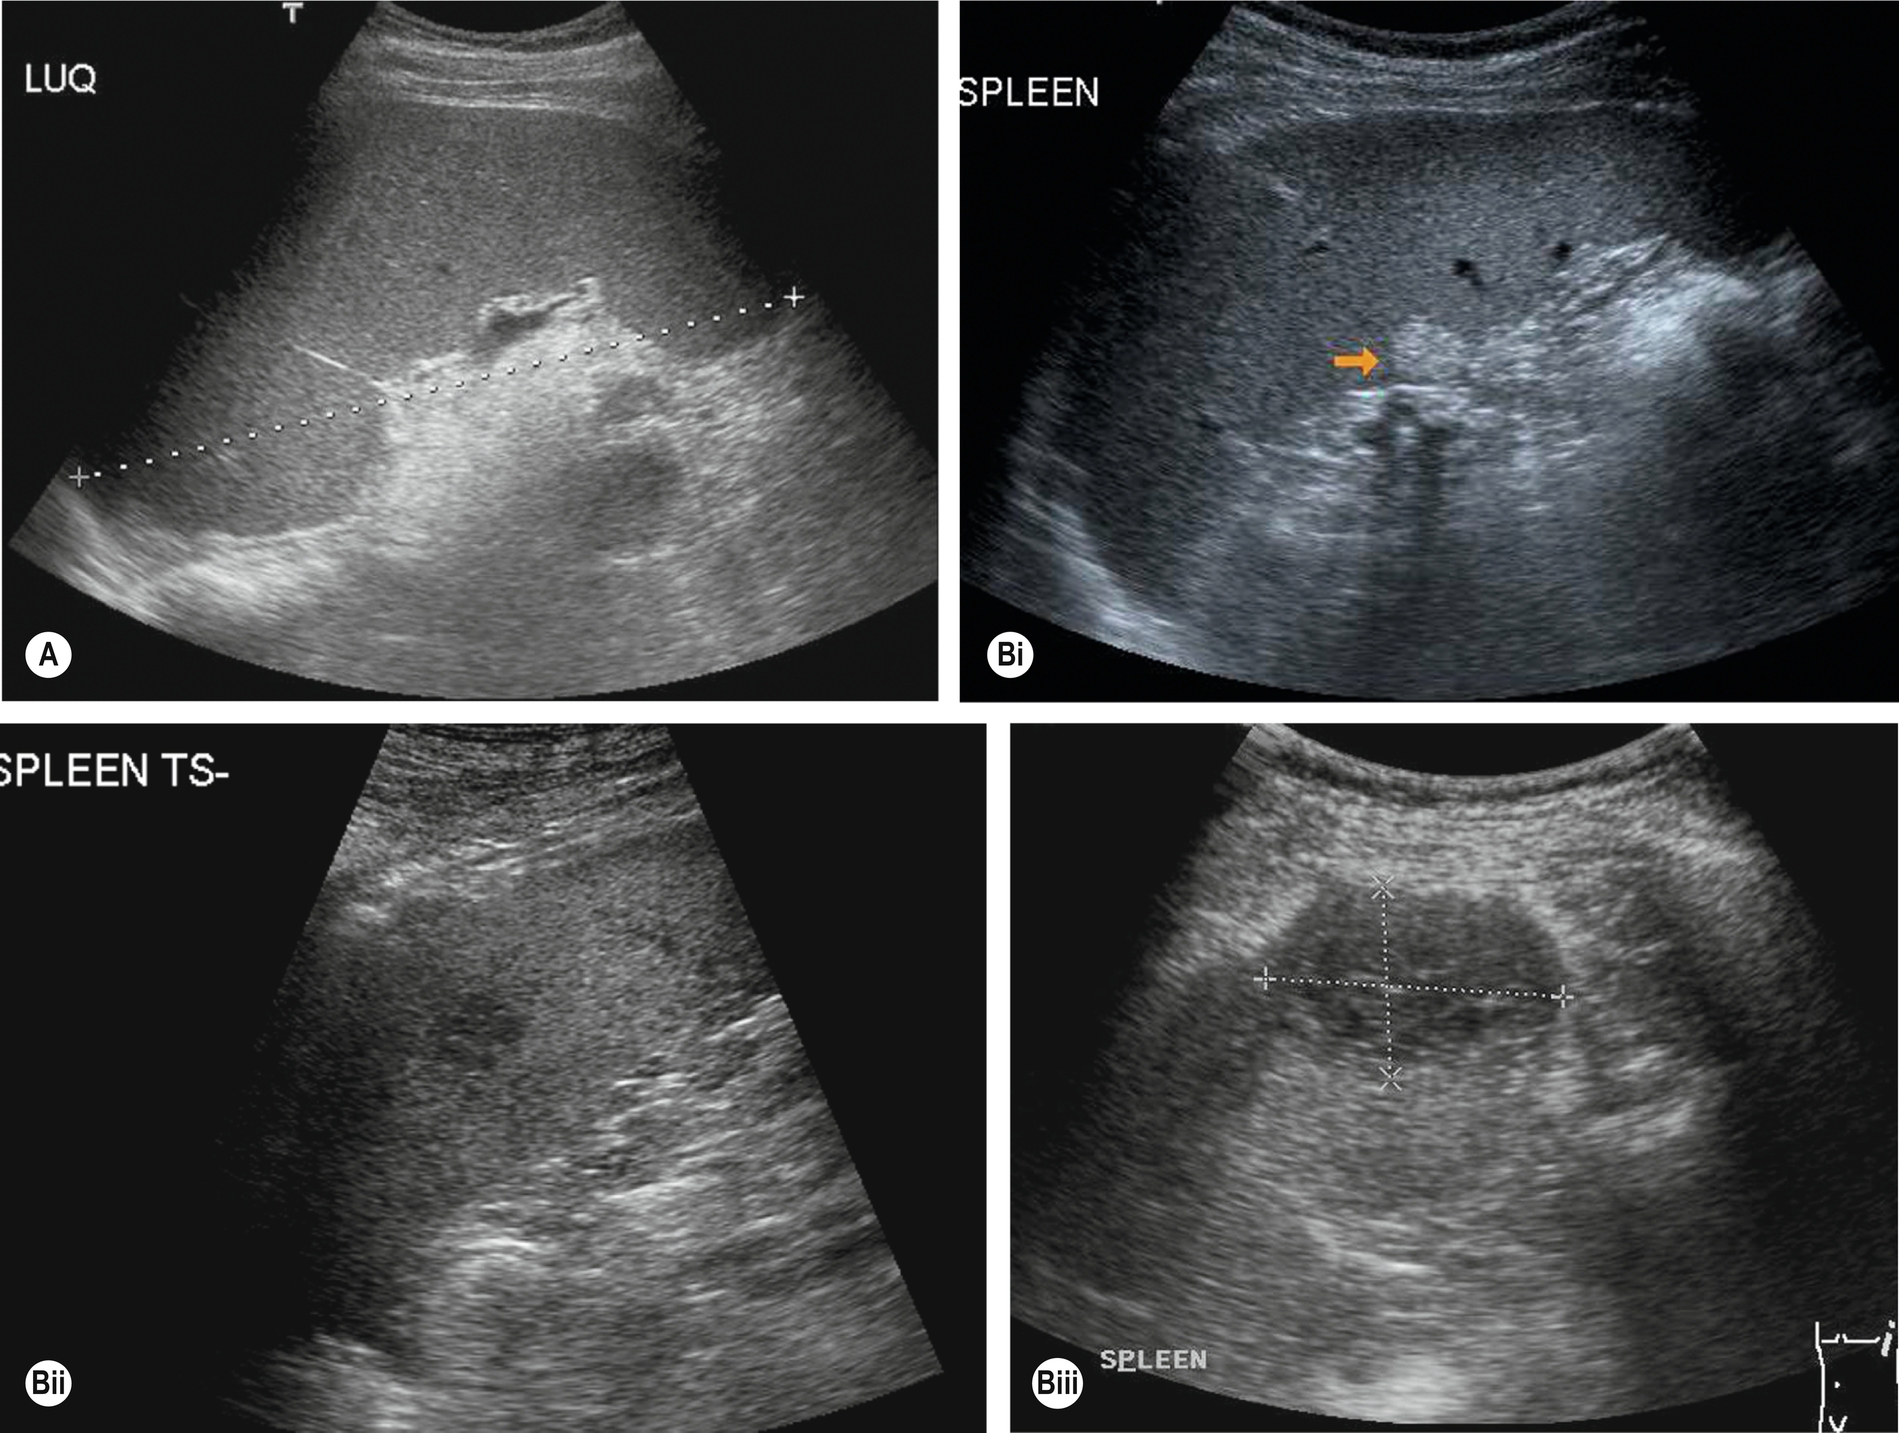

Measuring the length of the spleen is an adequate indicator of size for most purposes and provides a useful baseline for monitoring changes in disease status which is reproducible by the operator in subsequent scans and comparable to measurements obtained in cross-sectional imaging. Ultrasound is often the modality of choice in monitoring the spleen size because of lack of radiation and good operator reproducibility. A measurement of greater than 12 cm would be considered enlarged in most adults; however, as previously discussed, body size and type can impact the “normal” splenic size range. As the spleen enlarges, it extends downwards and medially. Its inferior margin becomes rounded (Figs. 5.1D–E, 5.2A), and it may extend below the left kidney and into the pelvis.

Although the cause of splenomegaly may not be obvious on ultrasound, the causes can be narrowed down by considering the clinical picture and by identifying other relevant appearances in the abdomen. For example, splenomegaly because of portal hypertension is frequently accompanied by other associated pathologic conditions such as cirrhotic liver changes, varices (Fig. 5.2B), or ascites. In cases of portal hypertension, it is important to assess the splenic vasculature to assess for varices at the hilum.

Splenunculi are typically small, well-defined ectopic nodules of splenic tissue and, therefore, are of similar ultrasound echotexture to the spleen (Fig. 5.2C–D) and rarely exceed 2 cm in diameter. Occasionally the vessels supplying the splenunculus can be seen using color Doppler, and in equivocal findings, contrast ultrasound can be used. Splenunculi enlarge under the same circumstances as those which cause splenomegaly and may also hypertrophy in post-splenectomy patients.

This is frequently accompanied by portal vein thrombosis and results from the same disorders. The most common of these are pancreatitis and tumor thrombus. Color and spectral Doppler are an invaluable aid to the diagnosis, particularly when the thrombus is fresh and therefore echo-poor. Contrast agents may be administered if doubt exists over vessel patency. Splenic vein occlusion causes splenomegaly, and varices may be identified around the splenic hilum.